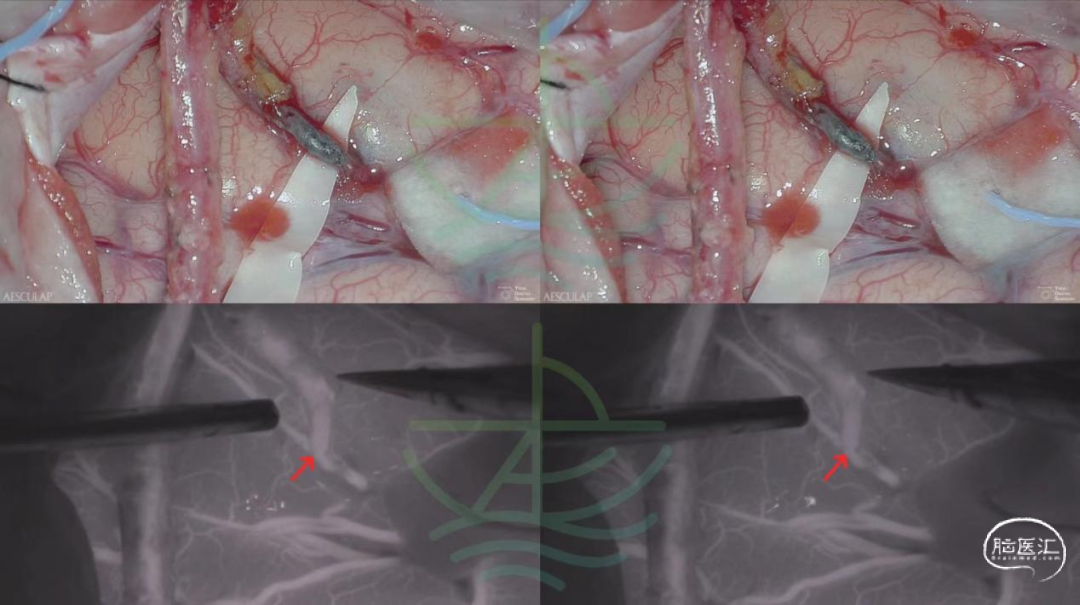

主刀的脑血管搭桥实战病例

(直接式脑血管搭桥治疗颈内动脉慢性闭塞,术中采用“试验性”血流阻断技术)

(联合式脑血管搭桥治疗经典烟雾病,术中采用“试验性”血流阻断技术)